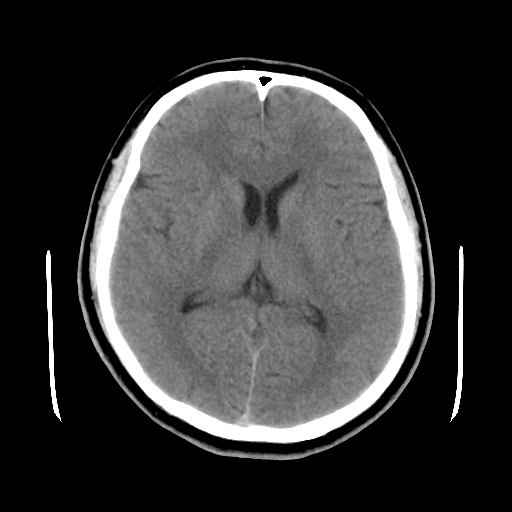

标题: CT15194:男,53岁,头痛、恶心三天。 [打印本页]

男,53岁,头痛、恶心三天。

筛窦囊肿、颅内未见明确异常

支持左侧筛窦后组粘液囊肿。